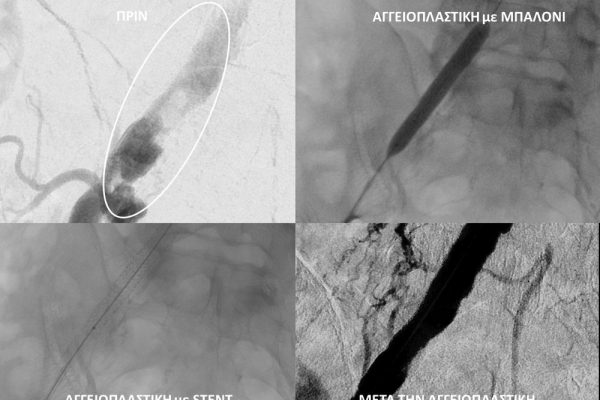

- Η αγγειοπλαστική των αρτηριών είναι μία μη χειρουργική επέμβαση που αποσκοπεί στη διάνοιξη των στενωμένων ή αποφραγμένων αρτηριών. Γίνεται με την ίδια τεχνική όπως και αγγειογραφία. Η αγγειοπλαστική των αρτηριών μπορεί να γίνει είτε με απλή διάνοιξη της αρτηρίας που εμφανίζει στένωση με μπαλόνι ή και να συνοδευθεί από τοποθέτηση ενδαγγειακής πρόθεσης (stent).